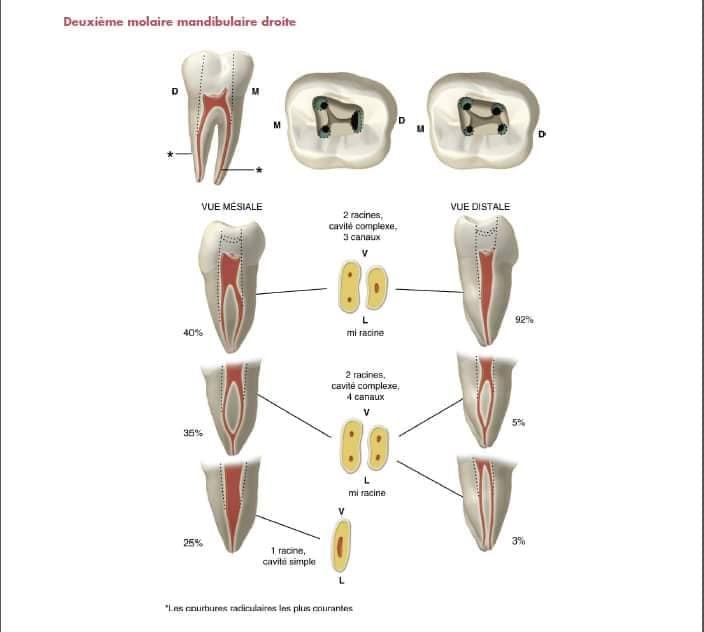

Deuxième Molaire Mandibulaire

Simplification : les canaux mésiaux se rapprochent

Forme : cavité d’accès rectangulaire

Facilité : anatomie moins complexe que la première molaire